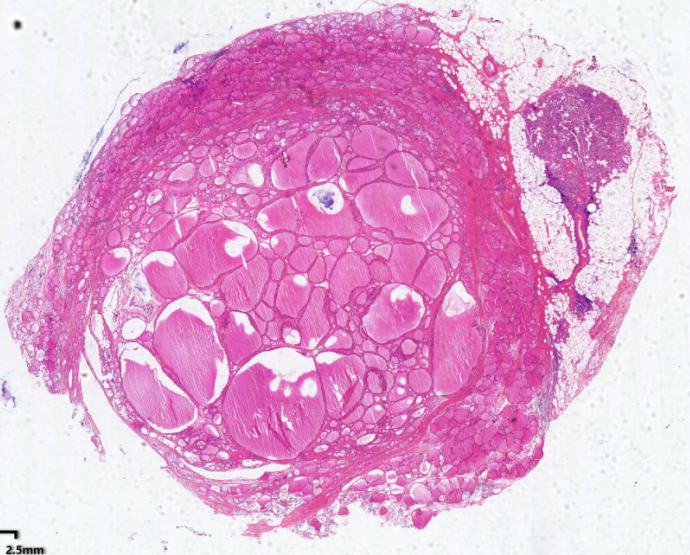

弥漫性非毒性甲状腺肿:甲状腺滤泡明显扩张,内含大量胶质,滤泡上皮细胞受压呈扁平状。部分上皮增生,可见小滤泡和小假乳头形成。

1.全景图

![]()

2.纤维组织包膜

3.滤泡上皮增生

4.滤泡扩张